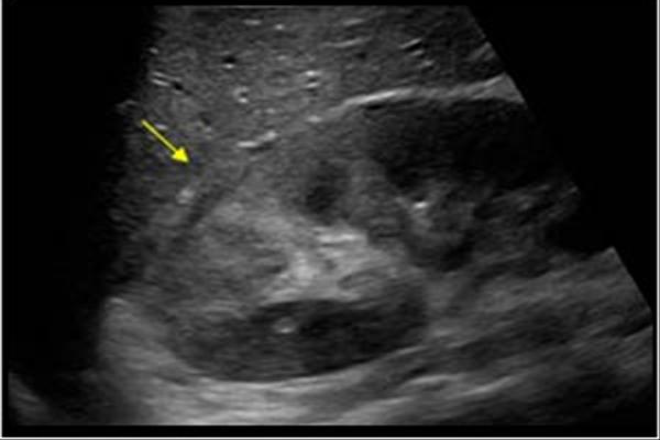

Sarcoidosis y carcinoma fibrolamelar del hígado

La sarcoidosis es una enfermedad de etiología desconocida que se caracteriza por la acumulación en los tejidos afectos de linfocitos CD4+ y monocitos, así como la presencia de granulomas no caseificantes que conducen a la alteración de la arquitectura tisular normal. En los lugares afectados la sarcoidosis se caracteriza por